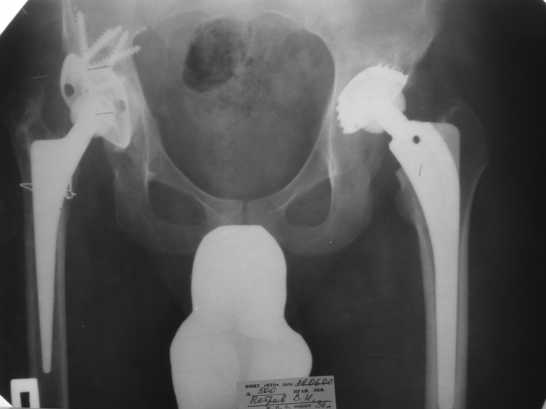

2005 г. при падении с высоты - перелом бедра в верхней трети, наложение АВФ . 3 года пациент ходил с аппаратом(рис. 3).